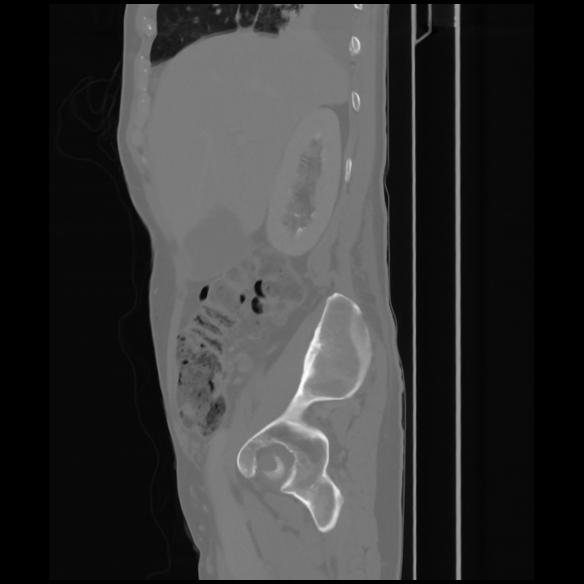

7 CUERPO,CE,Sagittal,3.000,CUERPO,Sagittal,